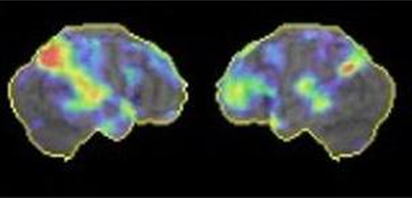

アミロイドPET(図2):当院で実施可能です。アルツハイマー病の原因物質と考えられているアミロイドβプラークが、脳内に溜まっているかどうかを調べる検査です。抗アミロイドβ抗体薬を使用するには、アミロイドPETが陽性である必要があります。

図2 アルツハイマー型認知症のアミロイドPET

アルツハイマー型認知症のアミロイドPET